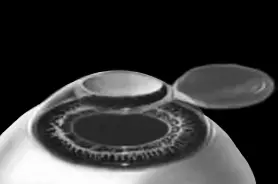

Стоит один раз моргнуть и лоскут скомкается и зрения не будет. Его бы пришить на место. Но швы деформируют роговицу. Все проще. Лоскут разглаживают мокрым тупфером, прижимая его ровненько к старому месту (рис. 7 и 8). Только место не старое, с роговичного ложа удалили несколько микрон в виде причудливой ямки (при коррекции близорукости).

Рис. 7.При коррекции близорукости на роговичном ложе формируется «ямка».

Иллюстрация с сайта Международного лазерного центра www.optics.ru